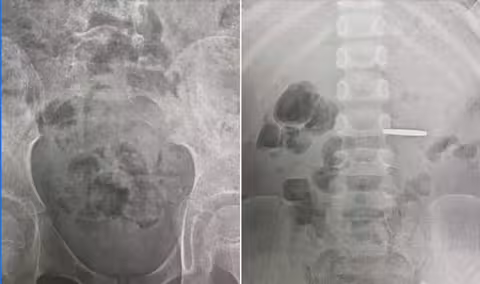

У шлунку дитини виявили дві монети. Лікар-ендоскопіст Марта Лучак діставала монетки без операції за допомогою ендоскопа під наркозом.

«Процедура була тривалою, бо у шлунку дитини була не 1 монета, а 2 — одна номіналом гривні і друга 50 копійок», — розповідає Марта Лучак.